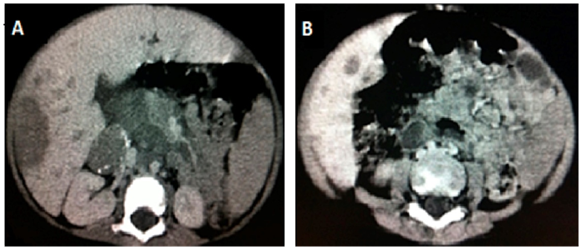

Blood count analysis showed leukocytosis (12800) and 153000 platelets. 7.6g/dl hemoglobin and 24.1% hematocrit. PCR: 34.32mg/L and ESR 76. Albumin: 3.45. Radiographic examination of the lower limbs visualized bone rarefaction of femurs, tibias, and fibulas (Figure 1).

Figure 1 X-ray of the lower limbs demonstrates the bone rarefaction of femurs, tibias, and fibulas